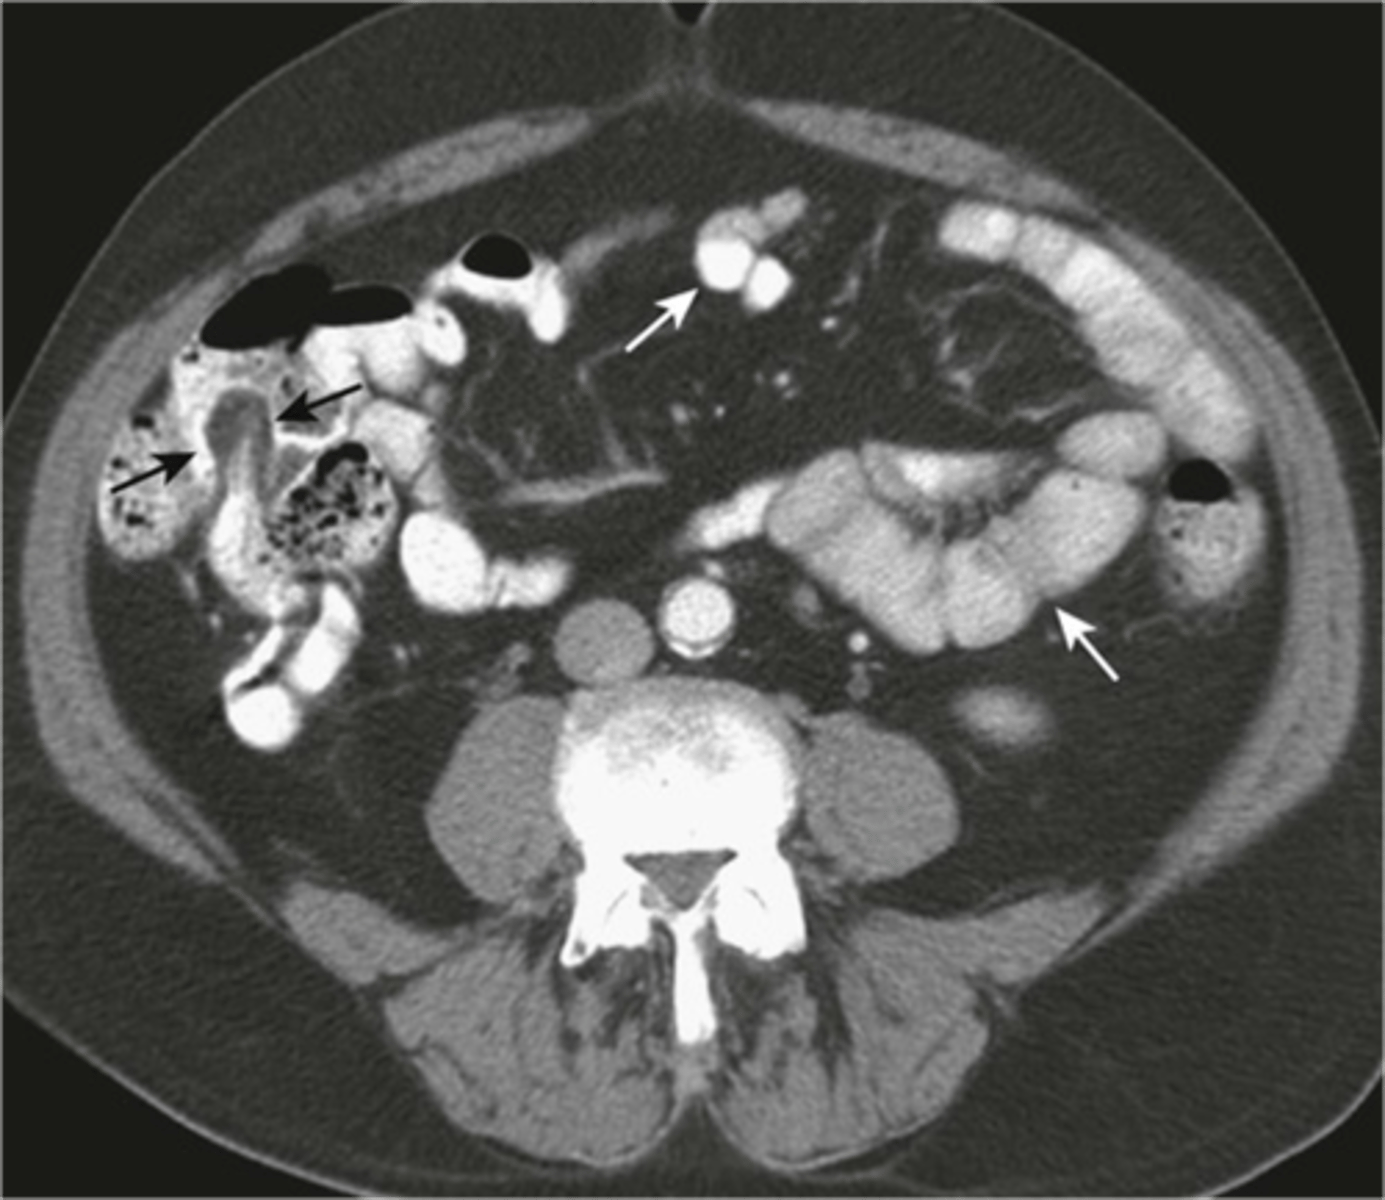

Normal small and large bowel on CT

Normal bladder CT